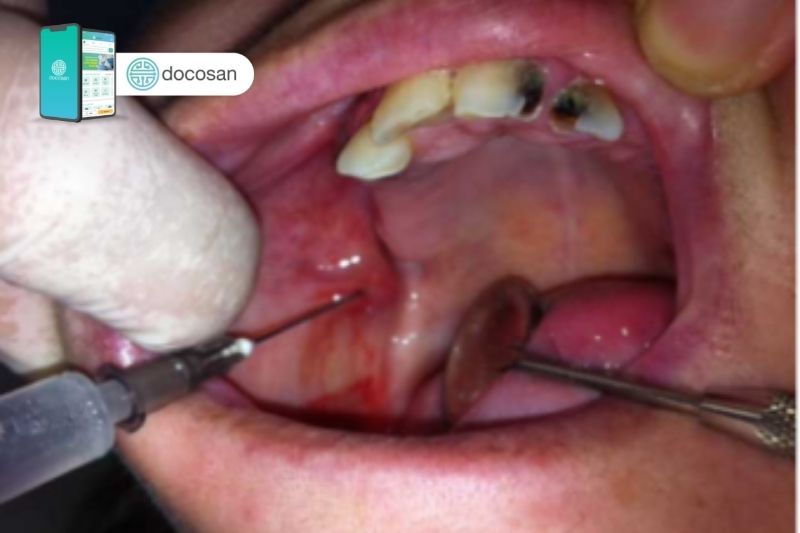

U máu trong miệng chiếm khoảng 10% các trường hợp u máu, nó tương tự u máu ở dưới da, có thể có dạng u phẳng, gồ lê hoặc thể củ. Thường không phát hiện có phình mạch trong niêm mạc khoang miệng.

U máu trong miệng thường xuất hiện ở các vị trí như môi, nổi cục máu trong má, lưỡi, sàn miệng, đặc biệt là vòm khẩu cái mềm, có thể lan đến cả amygdale và dính với lưỡi gà, hình thành một phức hợp u gồ, thể củ, tình trạng này tương đối nguy hiểm.

Niêm mạc phủ bền mặt u máu trong miệng có màu đỏ thẫm hoặc màu tím sẫm, có thể hơi gồ ghề nhẹ hoặc nhiều, dễ gây chảy máu khi bị đụng phải và gây vướng khi ăn uống hoặc nói chuyện, ảnh hưởng nhiều đến cuộc sống sinh hoạt và làm việc của người bệnh.

U máu trong miệng có thể lan rộng ra ngoài bề mặt da, sau khi nó xâm lấn đến tổ chức dưới niêm mạc, tổ chức mỡ dưới da và cơ. Sự lan rộng thường theo chiều ngang, rải rác nhiều nơi trong khoang miệng.

Tuy nổi cục máu đông trong miệng không ảnh hưởng nhiều đến thẩm mỹ, nhưng hậu quả của nó là ảnh hưởng rất nhiều đến chức năng của người bệnh, gây vướng khi ăn, nói chuyện và gây chảy máu, có thể dẫn đến tình trạng nhiễm trùng vì khoang miệng là nơi có rất nhiều vi sinh vật.